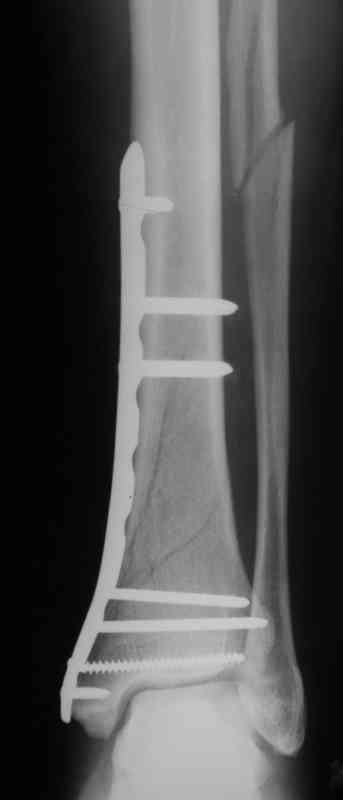

Выполнил MIPO предизогнутой метафизарной LCP

Красиво получилось, поздравляю. Насчет немедленной полной нагрузки, как на гвозде, про что Алексей Семенистый говорит - будете разрешать сразу?

Подход индивидуальный, учитывая массу больного около 130кг, разрешу частичную нагрузку 15-20кг, через 4нед. Rg-контроль, при отсутствии признаков нестабильности полная нагрузка

И все же немного критики:1) Вы добивались анатомичной репозиции, которая требует абсолютной стабильности, которая в свою очередь возможноа только в условиях межфрагментарной компрессии. Пластина уложена как мостовидная, не хватает стягивающнго винта. 2) есть укорочение малоберцовой кости, необхордимо восстановить ее длину! В таком виде я бы не стал разрешать раннюю нагрузку. Добавить самую малость: стягивающий винт и остеосинтез малоберцовой кости и больной может наступать сразу.

>Вы добивались анатомичной репозиции, которая требует абсолютной стабильности, которая в свою очередь возможноа только в условиях межфрагментарной компрессии. Пластина уложена как мостовидная, не хватает стягивающнго винта

Полностью с Вами согласен, если остеосинтез выполняется открыто, удаляется гематома с обл. перелома, требуется анатомиччная репозиция и аксиальная+межфрагментарная компрессия.

В этом случае остеосинтез выполнялся малоинвазивно и я не добивался абсолютной стабильности преднамеренно. Стабильность относительная и ст. её зависит от механических свойств импланта;возможно, нужно было взять длиннее пластину, увеличив её рабочую длину

> есть укорочение малоберцовой кости, необхордимо восстановить ее длину